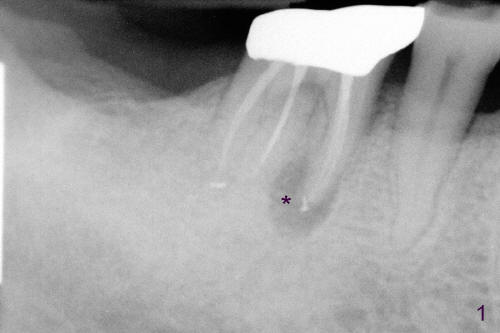

如以前介绍()右下第一磨牙近中根尖阴影根管治疗后逐渐增大(图一*),最后病人同意做根切,术前颊侧观显示近中根尖处肿胀(图二*),前庭沟挺深的,暴露可能不错(金杭晴理论),但如何做切口呢?根尖附近半月形切口(图三),还是牙龈沟切口附加斜形切口(图四)?结果

Probably due to our similar background (oral surgery), I chose surgical mode. I particularly like your idea: 根切的关键在于前庭沟浅还是深,深好做,因为暴露好。In fact the vestibule is deep in this case as will be shown soon in my web. What incision should I make, gingival sulcus or apical semilunar, for the best exposure? Xin Fri, 3 May 2013 18:22